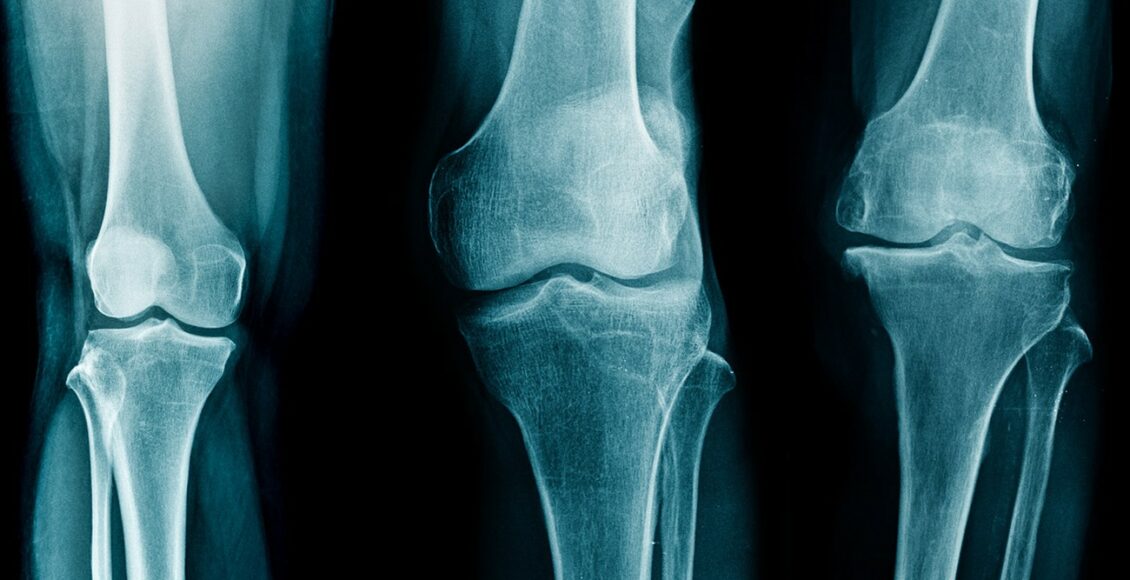

Des chercheurs développent une technique d’imagerie capable de voir les os et les tissus mous à la fois, utile pour détecter l’arthrose en amont, annonçait l’Inserm le 3 janvier passé.

D’ après la même source, les chercheurs travaillent sur une nouvelle technique, appelée « imagerie par contraste de phase aux rayons X ». Cette technique permet de voir les os, d’une part, mais « elle mesure également la déviation des rayons X par les tissus, que l’on appelle “réfraction” ».

« Les tissus mous et cartilagineux dévient 2 000 fois plus ces rayons qu’ils ne les absorbent. Ainsi, ils apparaissent aussi sur les images obtenues », rappelle l’Inserm.

Cette méthode d’imagerie, l’ICP, permettrait d’avoir des images plus claires, plus complètes, avec davantage de détails que les techniques traditionnelles. Elle évite d’avoir besoin de réaliser un IRM, une échographie et une radio sur une même partie du corps pour analyser les tissus denses et les tissus mous.

Les micro-calcifications sont par ailleurs plus visibles. Le système est par contre très onéreux à mettre en place, les chercheurs estiment qu’il pourrait être disponible d’ici 5 ans.